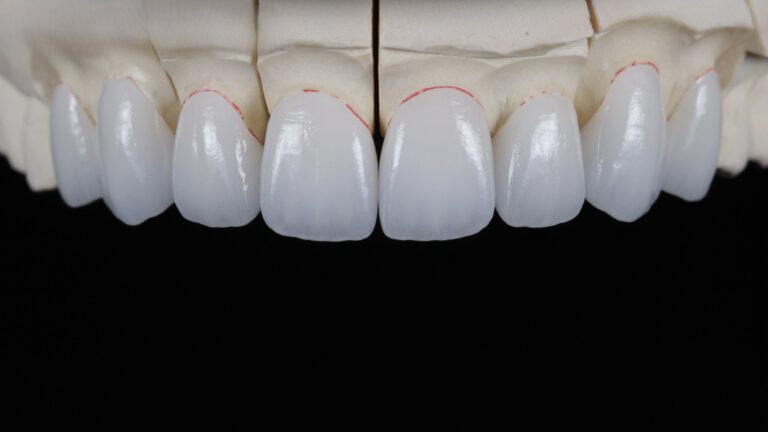

Veneers

Ceramic veneers restoration refers to a restoration method in which a thin layer of porcelain is bonded to the surface of the teeth to improve the color, shape and aesthetics of the teeth.

Common Forms: Traditional ceramic veneers, Ultra-thin veneers, Partial veneers repair.

Indications:This is suitable for restorations of front teeth that are discolored, slightly damaged, have large gaps between teeth, have poor shape, or require high aesthetic standards.